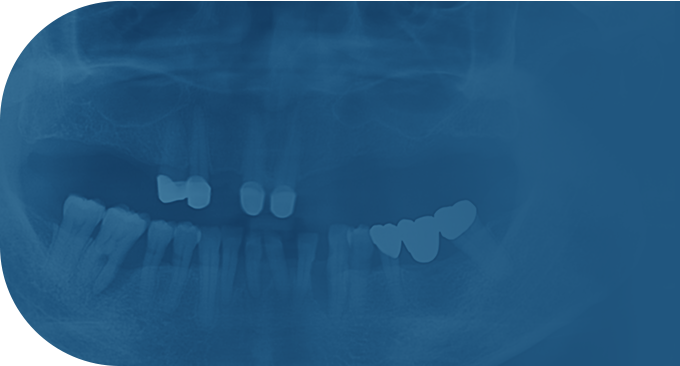

치료사례

임플란트 치료사례

*모든 증례 사진은 의료법 제23조, 제56조에 의거하여, 당사자의 동의하에 게시하였습니다.

*치료 사진은 모두 본원에서 치료한 환자분의 사진입니다.

*치료 사진은 모두 동일인의 사진이며, 동일조건에서 촬영하였습니다.

*개인의 차이에 따라 시술 및 수술 후 부작용이 발생할 수 있으며, 의료진과 충분한 상담을 받으시기 바랍니다.